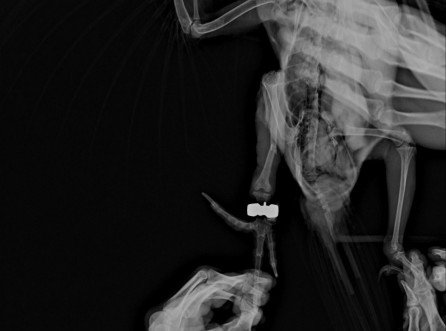

앵무새 다리(경골)골절

홍금강 경골골절 치료